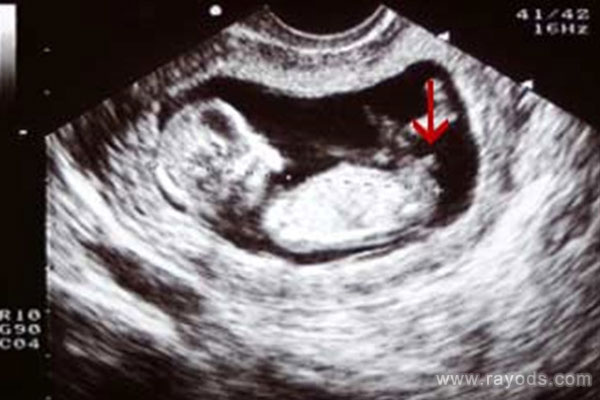

胎囊形状看男女(超准) 生了男孩当时42天孕囊

在怀孕以后,爸爸妈妈们讨论最多的一件事情就是宝宝的性别了。虽然知道生儿生女的是一样的,也知道10个月以后就知道答案了。但就是按耐不住内心的那种好奇。就很想知道肚子..